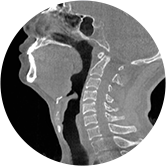

• 气道

• 颈椎